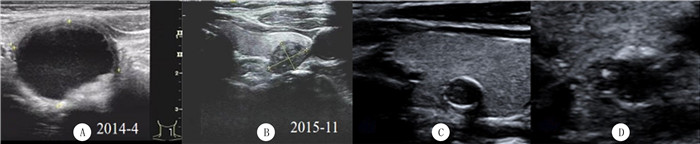

2 MNs的高频超声声像图特征 2.1 体积缩小体积缩小(图 1A、B)是MNs最特异也是最有诊断价值的特征。KOO等[14]发现FNA后,88%(29/33例)MNs出现体积缩小。LACOUT等[7]的研究结果也显示,在12~61个月(平均28个月)的密切随访期间,MNs的体积缩小比例约为45%。

![]() |

| A、B为1例病人甲状腺结节体积缩小观察。A:2014年4月左叶囊性为主的结节,最大径为2.7cm;B: 2015年11月复查,结节体积缩小,最大径为1.0 cm,并出现“双边征”及内环上点状钙化。C、D显示甲状腺结节钙化。C:结节周边不连续壳状钙化;D:放大图像后,观察到钙化外有确切的实性低回声成分,手术病理证实为PTC。 图 1 MNs体积缩小和不连续钙化的高频超声声像图特征 |

2.4 钙化表现MNs中可出现多种钙化,包括弧形/环形/壳状钙化、粗大钙化和微钙化等[14]。弧形/环形/壳状钙化多出现在结节周边,是结节木乃伊化的终末阶段[7]。然而,当壳状钙化不连续或钙化外有确切的实性低回声成分时,要警惕恶性的可能[29](图 1C、D)。粗大钙化多位于结节的中心或略偏心,多是原囊实性结节中实性成分发生退变和钙化所致。微钙化大部分是结节囊性成分中的胶质浓集而成,多位于中心或偏心部、聚集分布,周围多有小囊变区和“彗星尾”征[14, 30-31]。